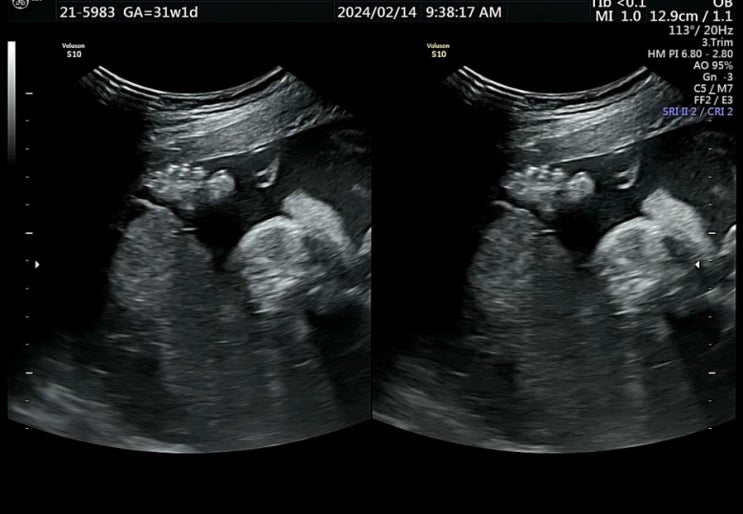

임신기록 31~32주 | 배뭉침 병원방문, 태아 몸무게 늘리기 성공?

31주차 증상 - 화장실 자주감 - 31주차 +10kg 돌파, 태아 몸무게 1.7kg 일주일만에 500g 살크업 성공 ? ...